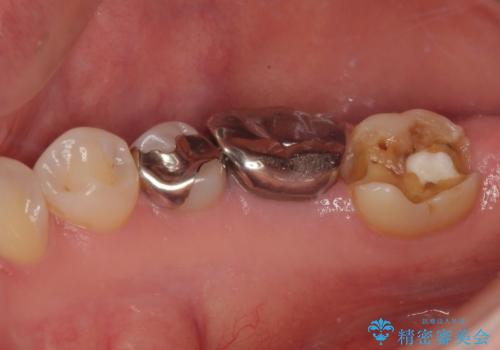

- 右下の銀歯が取れたとのことで来院された患者様です。脱離をしたメタルインレーを戻してみましたが不適合を認めました。メタルインレーの範囲が大きく、残っている歯の範囲を考慮してオールセラミッククラウンにて補綴治療を行っていくことにしました。

拡大鏡視野下で虫歯の除去を行い、オールセラミッククラウンに適した形に整えました。